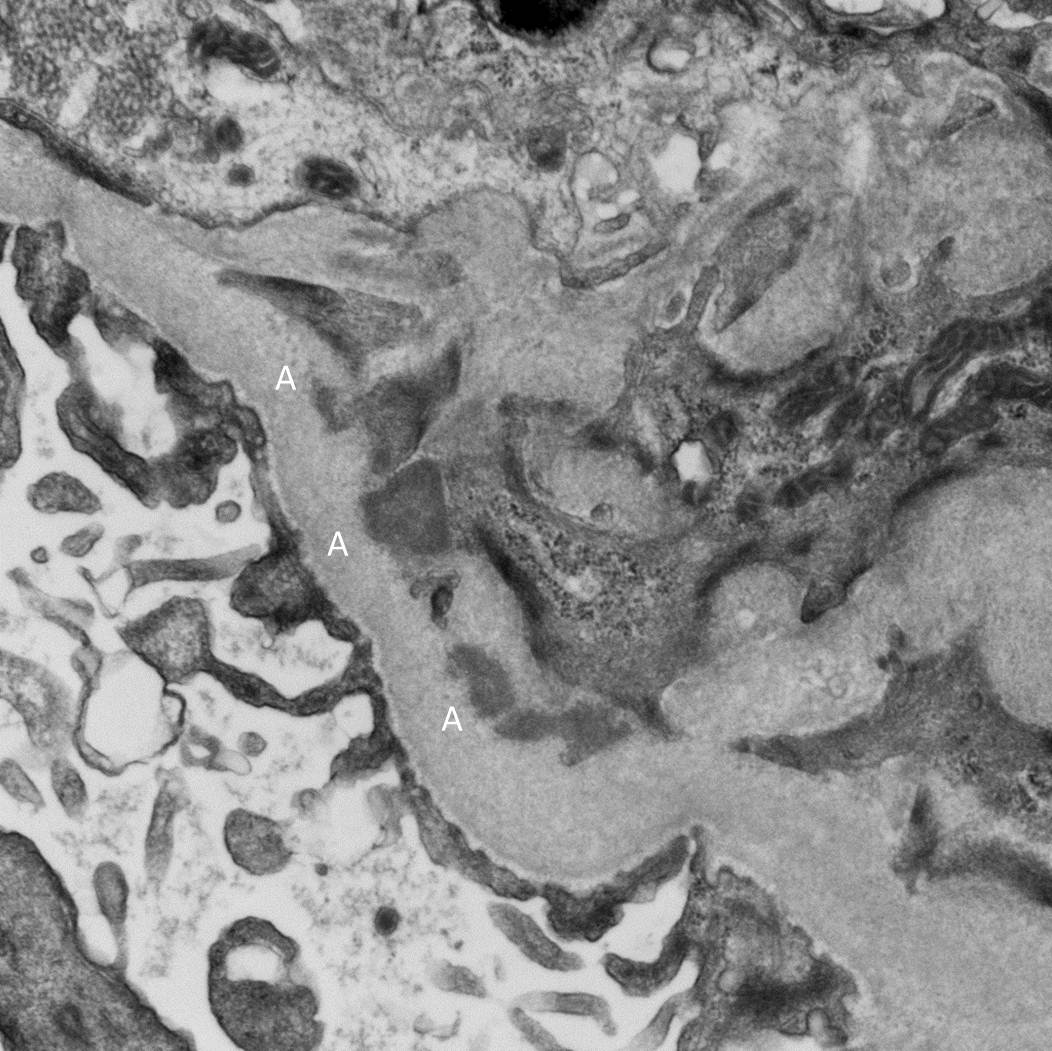

This image again shows a hypoperfused glomerulus. However, the main finding here is an extremely damaged arteriole (A). There is multilayering within wall of the vessel (that was replicated throughout the biopsy). The vascular lumen is almost occluded with endocapillary proliferation and remodeling of the vessel wall.

Finally, the EM showed multiple mesangial deposits (A) of uncertain significance but again, no evidence of membranous disease. Notably, there were was no evidence of active inflammation in the biopsy.